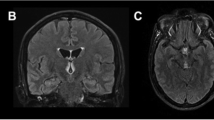

Atypical findings were observed in 23% of cases (n = 11/47), showing symmetric signal changes in the following locations: fornix, n = 4/47 (9%), cerebellar peduncle, n = 2/47 (4%), cerebral cortex, n = 1/47 (2%); internal capsule, n = 1/47 (2%); visual pathway, n = 1/47 (2%); junction area of the mammillo-tegmental and habenulo-interpeduncular tract, n = 1/47 (2%) and the brainstem/cranial nerve nuclei, n = 1/47 (2%) (see Table 1). Two out of three (67%) non-alcoholic and four out of 44 (9%) alcoholic patients with WE showed an involvement of atypical lesion sites (Figs. 6, 7 and 8).

Circumscribed possible involvement of the junction area of the mammillo-tegmental and the habenulo-interpeduncular tract (directly above the red nucleus) in a 28-year-old male non-alcoholic on a hunger strike (a, arrow; coronal fluid-attenuated inversion recovery images). Follow-up MRI 22 days later (b) disclosed progressive punctuate hyperintense signal changes (arrow) despite vitamin B1 substitution; c incomplete lesion regression (arrow) on day 101 after resumed food intake in the meantime

Involvement of the frontal and precentral cortical grey matter with hyperintense signal conversion on axial fluid-attenuated inversion recovery images (a, arrow); b, c diffusion-weighted imaging, b = 1000 s/mm2 (b) with normal apparent diffusion coefficient (ADC) value on ADC maps (c, arrow) in a 49-year-old female alcoholic

Involvement of both fornices with hyperintense signal changes (a, arrow; axial fluid-attenuated inversion recovery; arrowhead: choroid plexus) with distinct enhancement on contrast-enhanced T1-weighted images (WI) (b before, c after administration of contrast agent, arrow; arrowhead: choroid plexus) in a 53-year-old male non-alcoholic; d, e diffusion-WI disclosing restricted diffusion (d b = 1000 s/mm2; e apparent diffusion coefficient map; mean (SD): 0.61 (0.16) × 10−3 mm2/s, black and white arrow. Control subject: mean (SD) 0.76 (0.11) × 10−3 mm2/s)

While almost all these findings were present on FLAIR images, one case involving the fornix showed clear signal alterations only on DWI. All these changes were only present in addition to the involvement of typical brain areas. Three patients (n = 3/47, 6%) displayed more extensive hyperintense lesions with a space-occupying pattern on FLAIR/T2WI and concomitant macrohemorrhages on T2*WI, either in the thalami (n = 1/47, 2%) and brainstem (n = 1/47, 2%), or combined in the PAG, tectal plate and thalami with rupture into the ventricles (n = 1/47, 2%) (Figs. 9, 10 and 11).